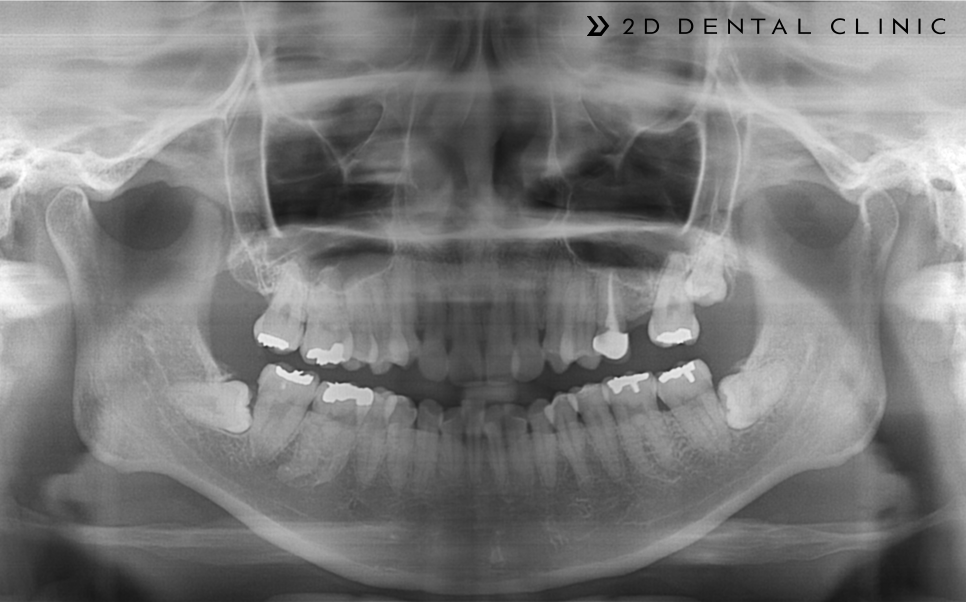

다시 전후 케이스 리뷰로 돌아와서! 본 환자분은 심한 크라우딩 상태에 상악의 제1 대구치(첫 번째 큰 어금니)가 없으신 상태셨답니다.

제1 대구치 자리에 제2 대구치를~

빈 공간을 임플란트로 채울 수 있는 옵션이 있지만 제1대구치 자리에 제2 대구치를 당겨서 빈자리를 채울 수 있게 진행했습니다.

전체 교정인 클리피씨로 진행되었고 상악의 양쪽의 제1소구치를 발치하였습니다. 제2 대구치는 미니스크류로 당겨드렸고요.